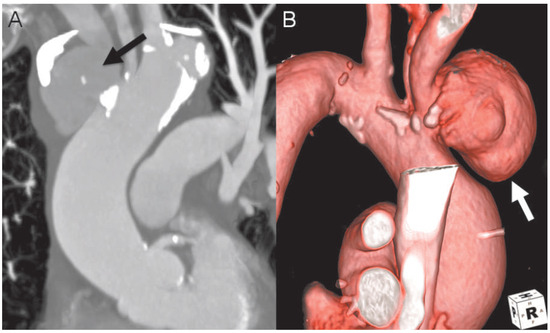

Simple Repair Technique for Rupture of the Brachiocephalic Trunk

by Grzegorz Zuk, Jens Bremerich, Friedrich Eckstein and Peter Matt

Cardiovasc. Med. 2015, 18(2), 68; https://doi.org/10.4414/cvm.2015.00320 - 18 Feb 2015

A 79–year-old woman with chronic obstructive pulmonary disease and history of severe arterial hypertension was admitted to our hospital due to recurrent chest discomfort and dyspnea [...] Full article